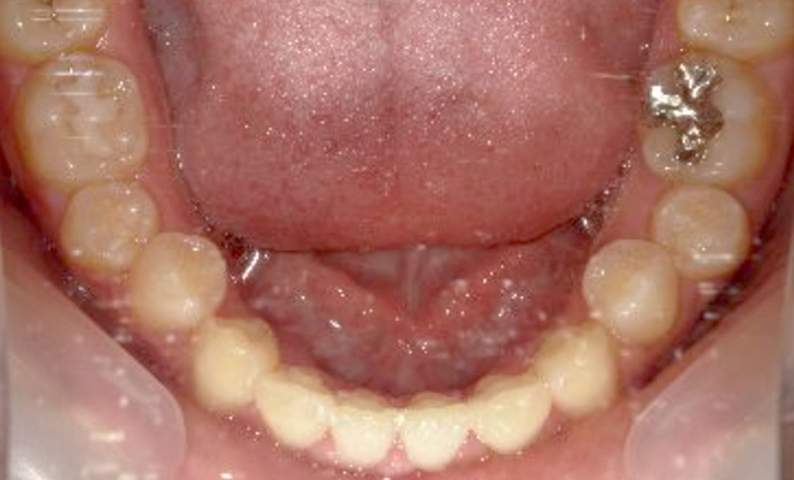

症例_004 上下顎の部分矯正

治療期間:8ヶ月金額:54万円+税女性前歯のガタガタ捻転歯

| Before | After |